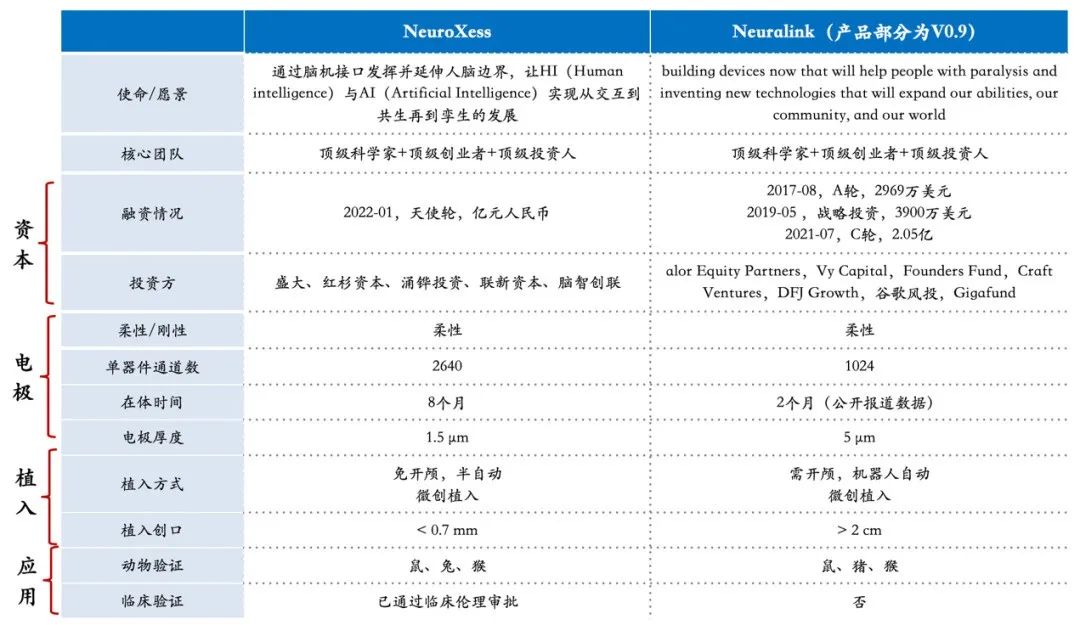

对标Nerualink,

(脑虎科技<NeuroXess>与Neuralink对比)

脑机接口是个会对人类未来产生颠覆性变革的领域,而其中的侵入式脑机接口被全球科学家公认是最硬核、门槛最高。在全球范围内,从事该领域研发的目前仅有美国的Neuralink、Blackrock等少数几家。作为中国侵入式脑机接口领域最具代表性的公司,脑虎科技充满信心地把马斯克的Neuralink作为全球性的赶超目标。

据了解,作为国家首批支持科研成果转化的试点单位,中科院上海微系统和信息技术研究所对脑虎科技给予了大力扶持。依托该所的前瞻战略布局与原创技术积累,脑虎科技在侵入式脑机接口领域已经完成了核心技术突破以及关键器件制造,已有产品在部分性能上超过了Neuralink,而且已经完成了动物试验,通过了相关伦理审批,将于今年一季度率先开展人体临床试验。

值得一提的是,脑虎科技现有产品的主材料,采用了蚕丝蛋白这一中国传统的材料,具有柔软、在体安全性高等独特优势。在去年的世界人工智能大会上,这一名为“免开颅微创植入式高通量柔性脑机接口系统”的核心技术,一举获得了最高奖“卓越人工智能引领奖”。